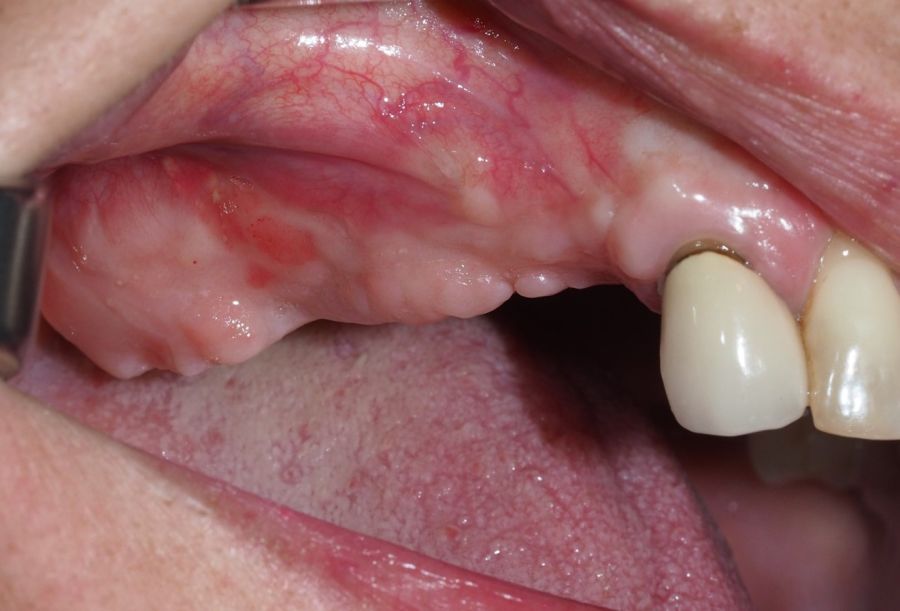

Transcurridas dos semanas, se procedió a la retirada de la sutura, observando una buena cicatrización de los tejidos blandos y ausencia de sintomatología sinusal. Se realizó control clínico y radiográfico al mes (Figuras 20 y 21), y a los 6 meses (Figuras 22, 23 y 24), donde se observó una correcta cicatrización mucosa, neoformación ósea y desaparición del pseudoquiste sinusal.